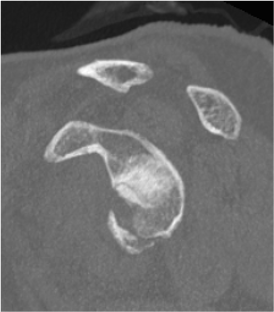

Bony bankart / glenoid rim fractures

Acute bony bankart / glenoid rim fractures

- ? acute repair to reduce instabilty

- ? avoid Latarjet procedure later

- systematic review of arthroscopic bony bankart repair

- 21 studies with 769 patients

- recurrent instability 12%

- return to sport 91%

Technique

Arthroscopic suture anchor fixation bony bankart